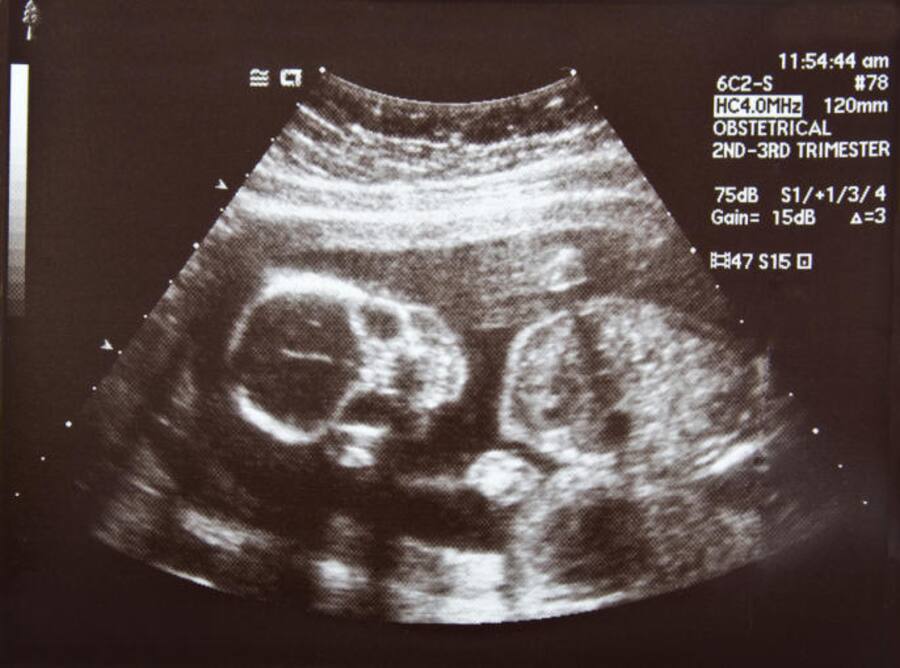

Non-invasive prenatal testing can be a boon in prenatal screening.

The incidence of chromosomal disorders in India is 1:166 live births. Given the large population, around 35,000 fetuses with Down syndrome alone are conceived every year. Therefore screening and diagnosis for chromosomal disorders are important in India as in other nations. The current methods for prenatal screening for chromosomal disorders are blood hormone levels and ultrasonography. These methods have low sensitivity and high false positive rate. They hence miss over 10% of an affected fetus. While invasive procedures like amniocentesis and CVS Chorionic villus sampling cannot be offered to all pregnant women as they pose a risk of miscarriage. NIPT on other hand is a screening test that analyses the cell-free DNA of the fetus and gives out a detailed report for any chromosomal abnormalities. The screening is non-invasive, extremely safe and is done by taking a small blood sample from the mother's arm. With detection rate over 99% and a false positive rate at 0.1 % there is a reduction of 50-70% in invasive procedures where NIPT is implemented. The incidence of chromosomal disorders in India is 1:166 live births [1].

Image source: Shutterstock